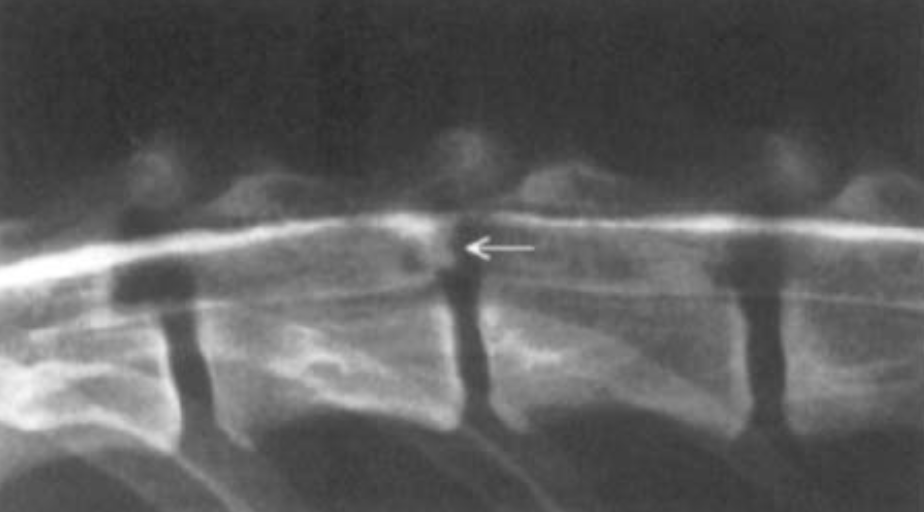

What is the incidence of myelomalacia? What are the myelographic signs?

What is the location of this contrast?

Subdural - characterized by smooth dorsal border and irregular ventral border of the contrast column; tend to accumulate dorsally in the vertebral canal; believed to be within the region of the structually weak dural border cells (subdural space)